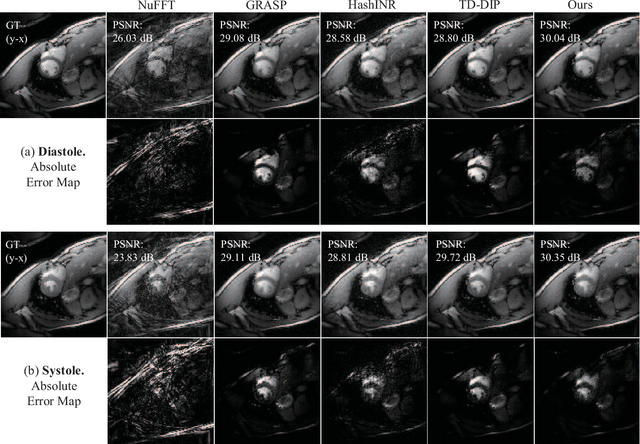

Abstract:Dynamic MRI reconstruction, one of inverse problems, has seen a surge by the use of deep learning techniques. Especially, the practical difficulty of obtaining ground truth data has led to the emergence of unsupervised learning approaches. A recent promising method among them is implicit neural representation (INR), which defines the data as a continuous function that maps coordinate values to the corresponding signal values. This allows for filling in missing information only with incomplete measurements and solving the inverse problem effectively. Nevertheless, previous works incorporating this method have faced drawbacks such as long optimization time and the need for extensive hyperparameter tuning. To address these issues, we propose Dynamic-Aware INR (DA-INR), an INR-based model for dynamic MRI reconstruction that captures the spatial and temporal continuity of dynamic MRI data in the image domain and explicitly incorporates the temporal redundancy of the data into the model structure. As a result, DA-INR outperforms other models in reconstruction quality even at extreme undersampling ratios while significantly reducing optimization time and requiring minimal hyperparameter tuning.